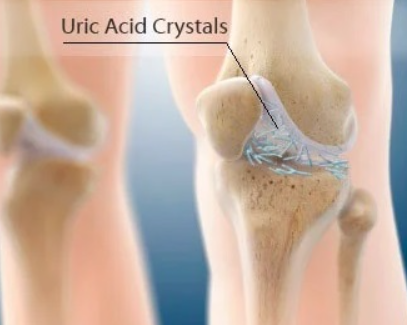

통풍: 요산 결정이 무릎에 쌓여 염증과 관절액 축적을 유발할 수 있습니다.

통풍, 활액낭염 등: 약물(통풍치료제, 스테로이드 등) 및 증상 조절.

배출된 관절액은 감염 여부, 결정(요산 등) 확인 등 진단에도 사용됨.

통풍이 원인일 경우 요산조절제 등